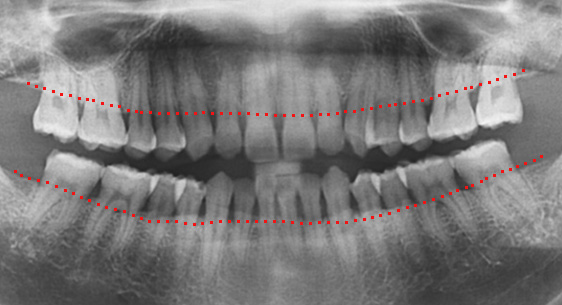

치조골이 절반만 남아있어도 치주치료를 통하여 자연치아를 살릴 수 있습니다. 타치과에서 임플란트 수술을 진단받은 경우에도

고운미소치과에서는 임플란트 수술을 안받고 치료가 가능하거나, 생각보다 훨씬 적은 수의 임플란트를 식립 하는 경우가 상당히 많습니다.